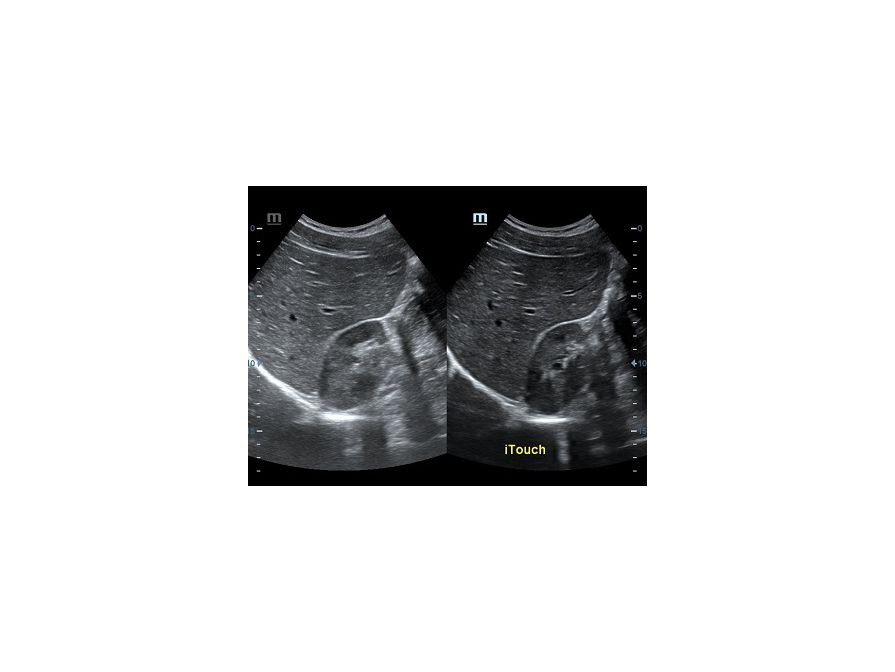

Обзор функции УЗИ: iTouch - автоматическая оптимизация изображения

Оптимизация изображения происходит и за счет постобработки. Наиболее часто используемый инструмент - общее усиление (Gain). Усиление делает изображение «ярче», но чем сильнее усиление, тем меньше различия между структурами. Также используются усиление по времени (TGC) и усиление по длине (LGC), которые позволяют изменять отображение на экране послойно, позволяя подсветить гипоэхогенные участки, или, наоборот, снизить визуально эхогенность слишком ярких моментов. Данный вид оптимизации требует много времени, для упрощения работы доктора на приборах Mindray внедрена система автоматической оптимизации - iTouch.